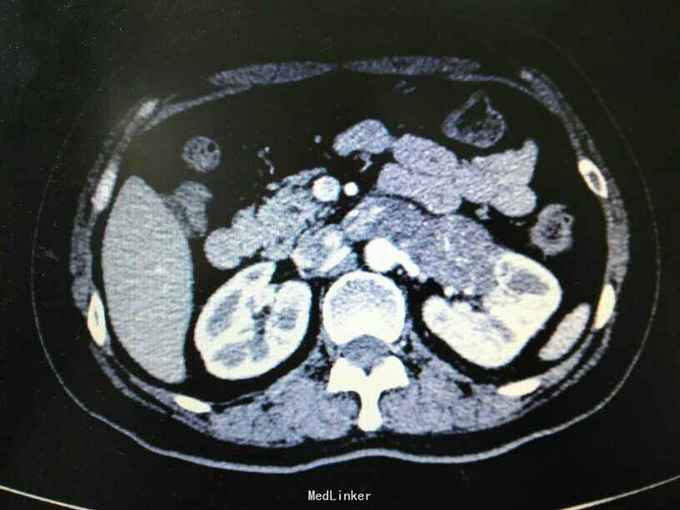

左肾门占位:癌栓?血栓?

女性,47岁,因“左腰1月,加重4天”,无血尿。无高血压,糖尿病等。

左肾区扣痛阳性。CT及MRI见图。

左肾静脉及腔静脉癌栓?血栓?;右肾上腺占位:髓样脂肪瘤?

诊断? 下一步治疗方案?